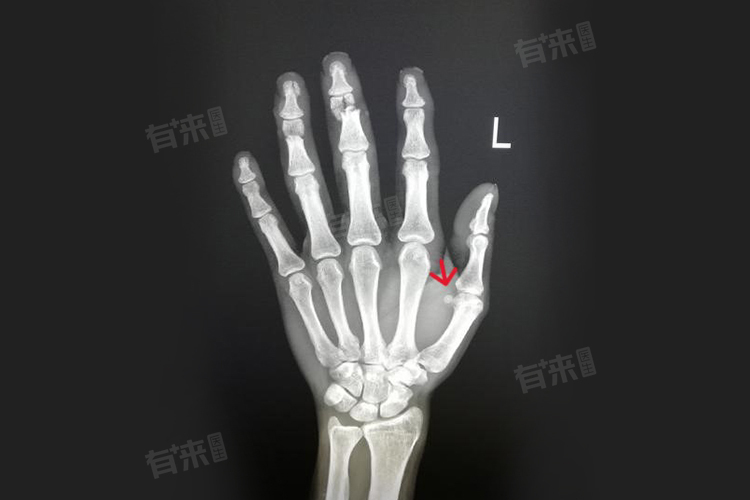

5、骨肿瘤:骨肿瘤虽不常见,但可使手指根部骨质异常增生,出现突出疙瘩。需进一步检查明确肿瘤性质。良性肿瘤多手术切除,恶性肿瘤则需综合治疗。定期对手指进行检查,发现异常及时就医。

- 骨科:若疙瘩质地坚硬,活动手指时伴有疼痛、活动受限,或曾有手部外伤史,可能是骨质增生、骨肿瘤、陈旧性骨折愈合异常等骨骼问题,需前往骨科。医生会通过触诊、X线等检查,判断骨骼状况,明确疙瘩成因。